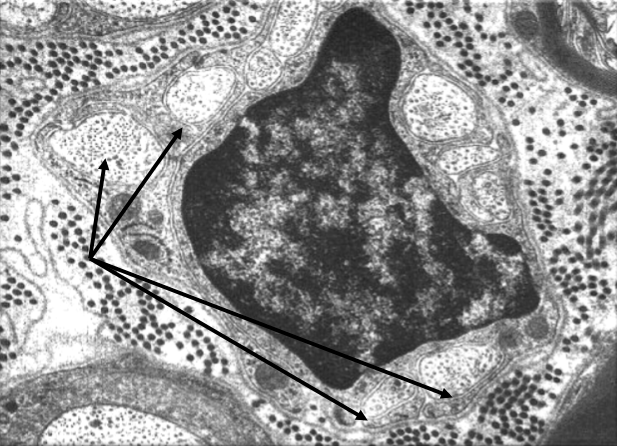

Voici l'image qui aurait du être dans ce sujet :

Du coup l'item A est bien faux ; et le D est faux car le noyau de la cellule de Schwann n'occupe pas toujours une position centrale par rapport aux neurones qu'elle soutient : dans les fibres myélinisées, il est périphérique.